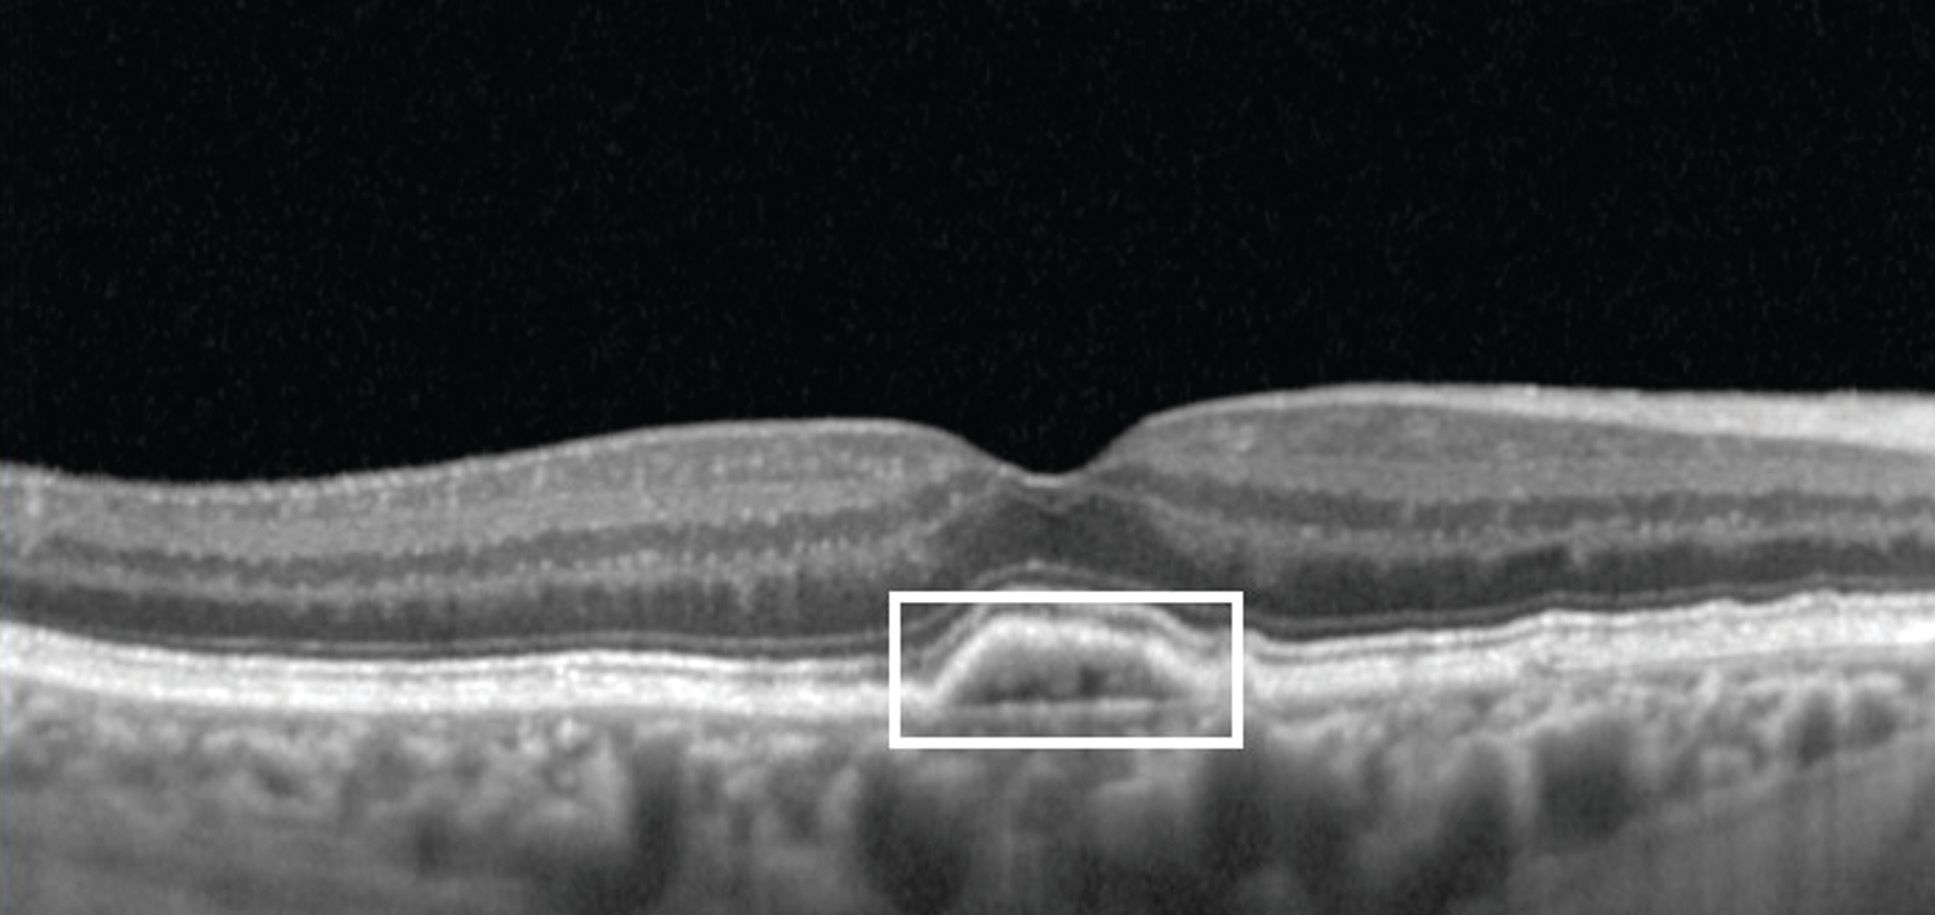

OPT-302 combined with ranibizumab: covering all the VEGF bases for superior visual gains compared with ranibizumab alone in wet AMD